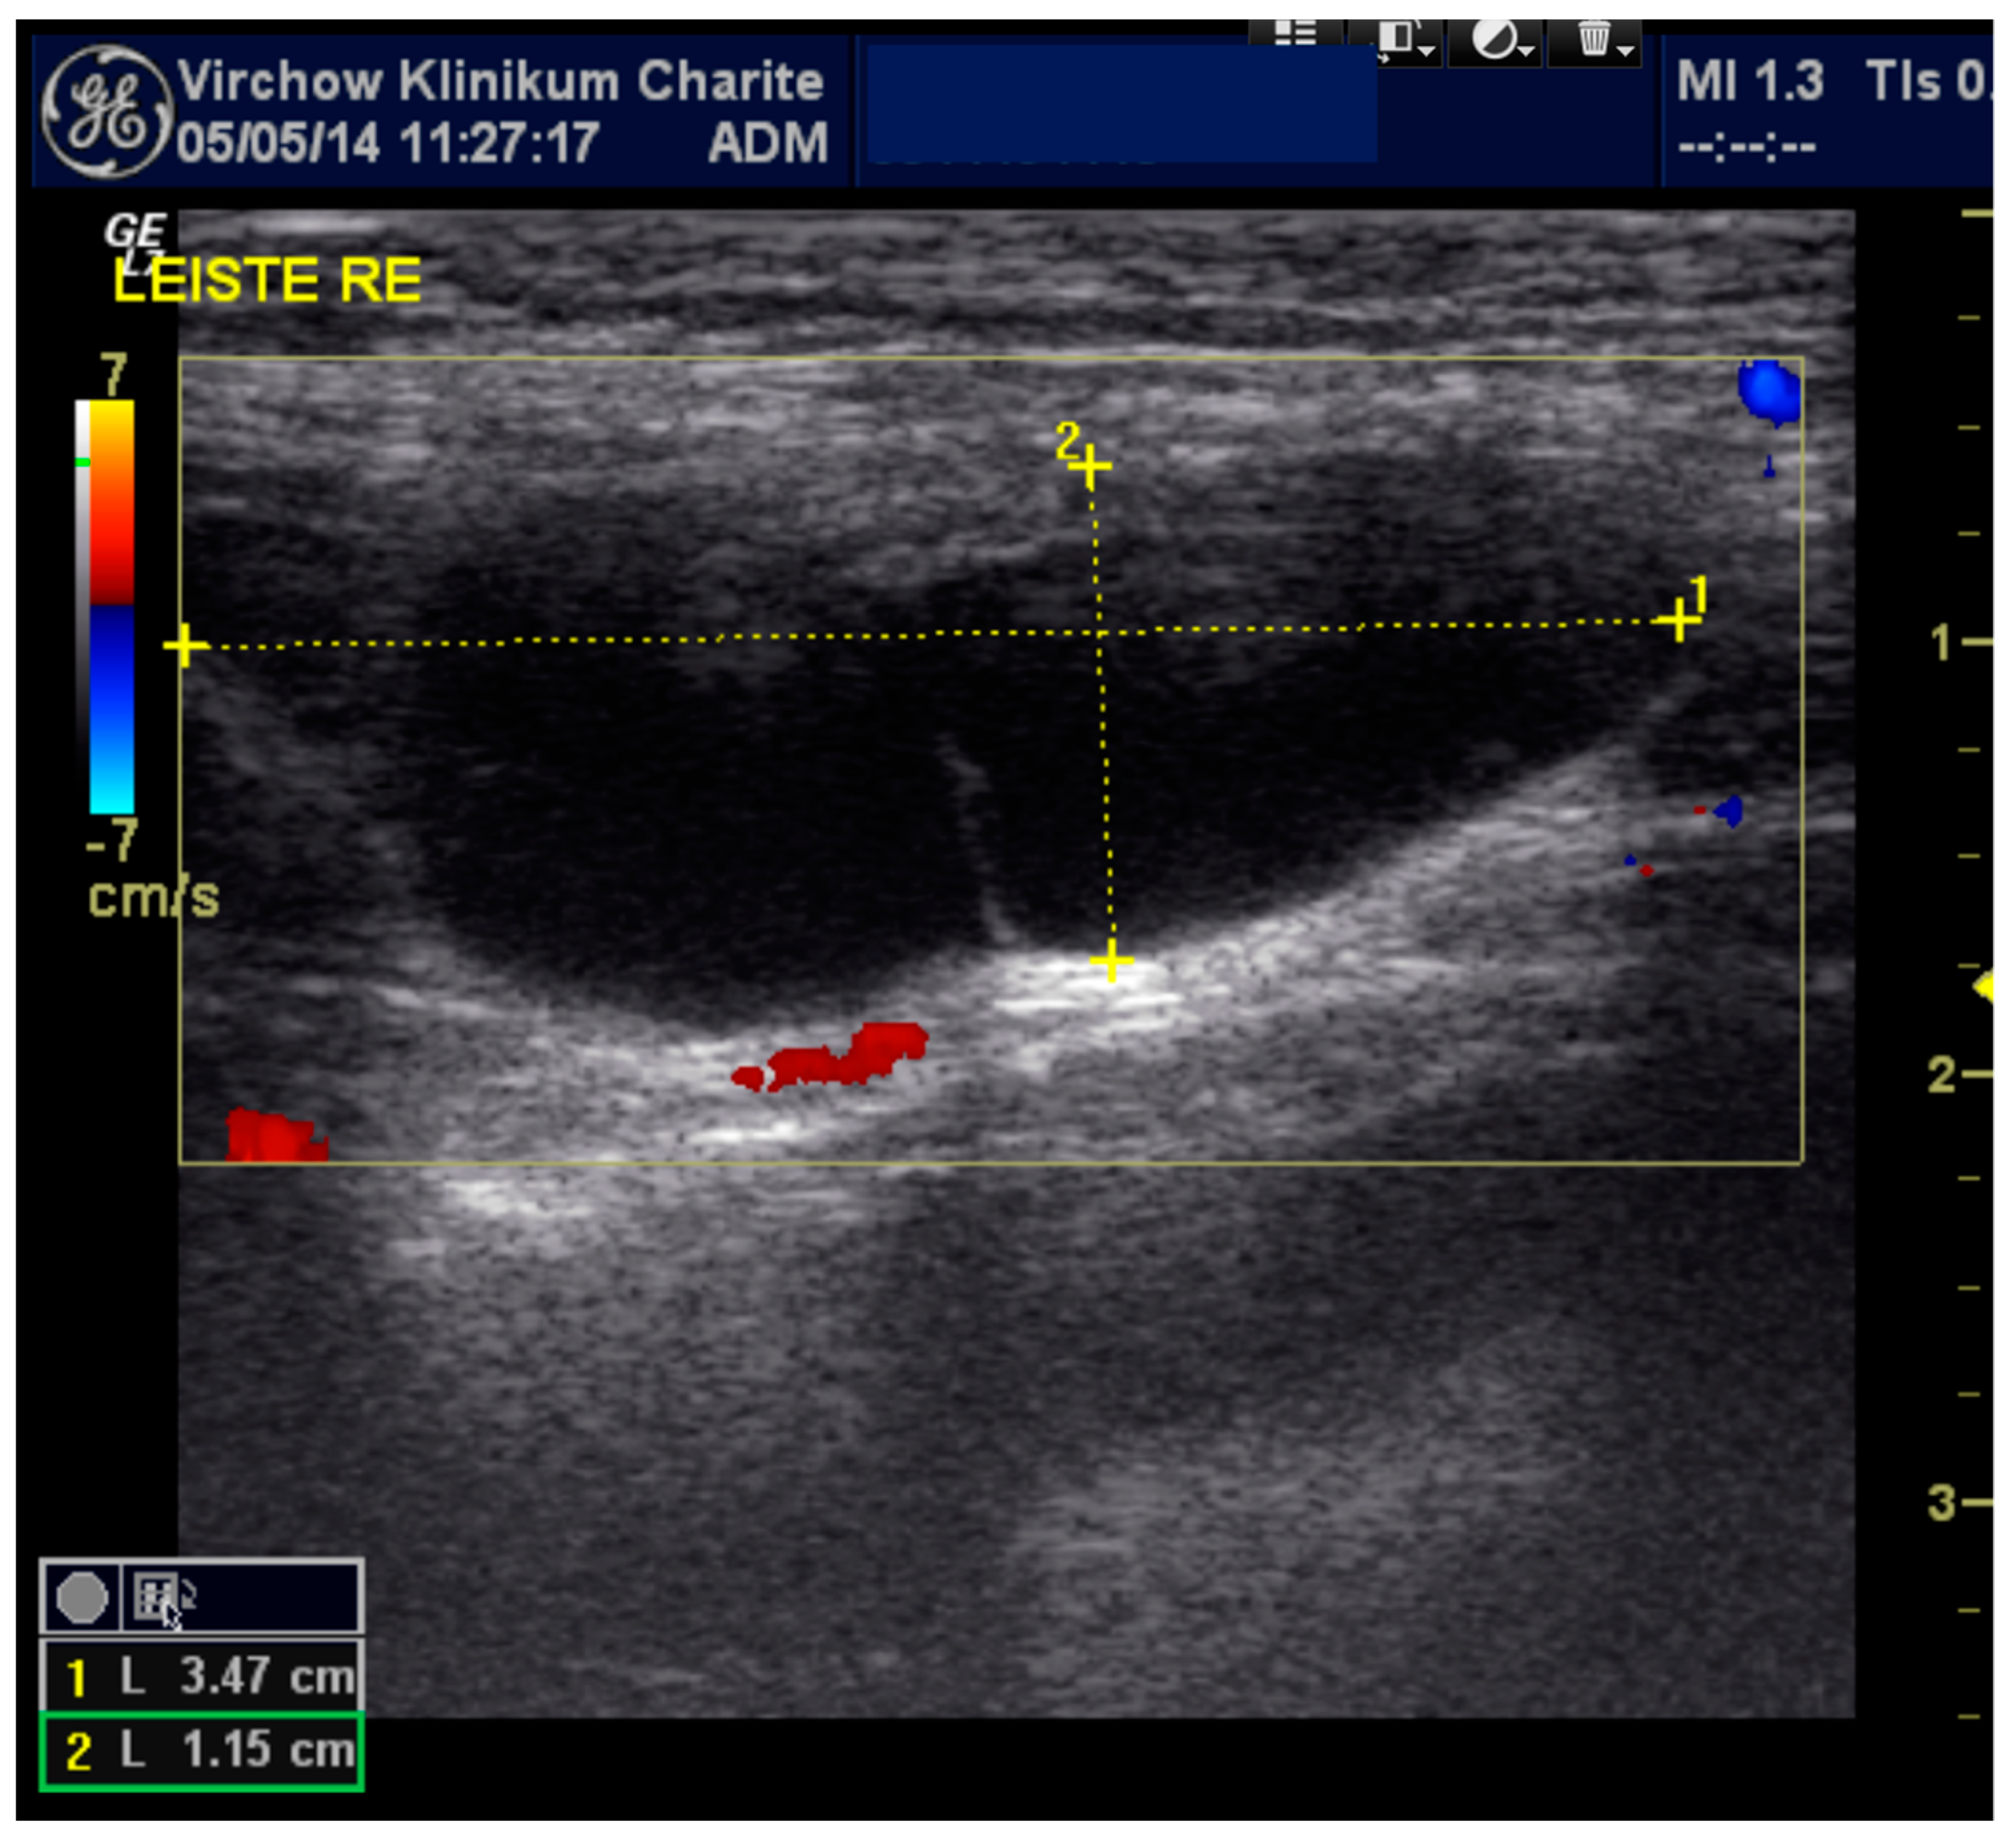

A 29-year-old female presented to a gynecological ambulance in 2014 with an unclear right-sided inguinal mass. She first noticed it because of pain after doing sports and visited a hospital. A small seroma measuring 3.47 × 1.15 cm in the right groin region extending towards the vulva was found by ultrasound (Figure 1). At that time, it had not been deemed as requiring puncture. Two years later, in June 2016, she noticed that the swelling was growing in size and presented again. The magnetic resonance imaging (MRI) finding in T2 weighted imaging of a 11.1 × 3.4 cm hyperintense mass without wall-enhancement of the contrast agent (Gadovist) now resembled a cyst rather than a seroma. It was punctured and 40 mL of serous liquid was aspirated. The results of the examination revealed mesothelial cells and lymphocytes matching the findings of a lymphocele with a connection to the abdominal cavity. Taking into account the location of the cyst the diagnosis of a Nuck’s hydrocele was made. The patient was referred to our clinic five months later, in November 2016, and underwent exploration, hydrocelectomy of the type 2 and TAPP (Figure 2 and Video S1) hernioplasty.

Figure 1.

Sonographic imaging of the right inguinal area: anechoic elongated fluid structure 3.47 × 1.15 cm.